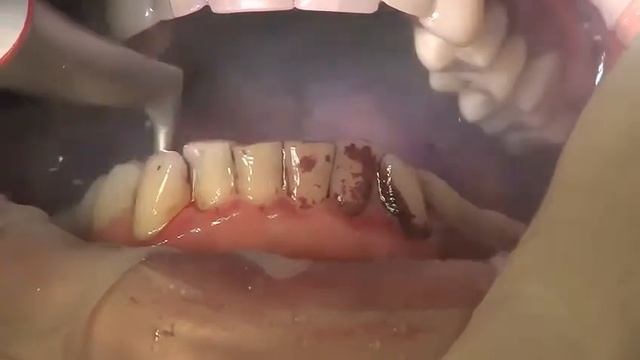

сегодня мы продолжим проводить чудесные химические превращения. смотрите до конца, что в итоге получилось!Guided Biofilm Therapy - curatarea profesionala in cabinetele stomatologice de indepartare a placii bacteriene, tartrului si coloratiilor.Basically Event Episode 4 lol🎨 Все больше успешных людей отдают предпочтение нейтральным и пастельным оттенкам, таким как бежевый, кремовый, белый и серый. Почему именно они? Эти цвета привносят в интерьер спокойствие, универсальность и легко сочетаются с другими элементами декора, позволяя создавать гармоничное пространство, в котором приятно находиться и работать. 💼 Не менее популярными становятся мягкие розовые оттенки, голубые и мятные, которые придают помещению особую уютную атмосферу и создают ощущение комфорта. Однако важно помнить, что выбор цветов – это вопрос индивидуальных предпочтений, стиля жизни и культурных особенностей каждого человека. 🌿 А какие цвета вы предпочитаете для своего интерьера? Поделитесь своим мнением в комментариях! Мы с удовольствием выслушаем ваши идеи и предложения. 💬✨5 ноября 2011г. клуб ВермельBlack and grey boxbraids rubber band method. Jumbo box braids. PRODUCTS USED: 1. Argon oil edge control: https://www.amazon.com/Creme-Nature-Argan-Perfect-Edges/dp/B007SG2QT2 2. Rubber bands: https://www.walmart.com/ip/Firstline-Sleek-Rubber-Band-Black-500-PK-500-0-PACK/25861225 3. 4 packs of Xpression hair: https://www.amazon.com/X-pression-Premium-Original-Braid-Colour/dp/B0054SCPPGChief Scientist Carl Nelson demonstrates how the combustion of hydrogen gas depends on the amount of oxygen present. A balloon filled with 100% hydrogen is ignited with a small flame. As the flame ignites the hydrogen gas, it combines with oxygen in the surrounding air. A large, but relatively slowly moving ball of fire is created. This is called a deflagration. Next, a mixture of two parts hydrogen and one part oxygen gas is used to create a foam of soap bubbles. The amount of oxygen available here makes a significant difference in the size and sound of the reaction. 2 H2(g) + O2(g) → 2 H2O(g) + Energy This reaction proceeds so quickly (a detonation) that a supersonic shock wave is generated. The sound level is significantly louder and the ball of flame generated is much smaller. Note that the final product of the reaction is water and energy.This a song production we have made for the "Pasko Ng Pagkabuhay" worship service of our church. It has a very clear message of the reason we are alive, is because Jesus Christ has RISEN from the dead. He has conquered death! For that, let us be thankful to Him, who is the Author and Finisher of our faith! Glory be to God in the highest!. --------------------------------------------------------------------------------------------------------------- SONG CREDIT ALL BECAUSE OF JESUS BY CASTING CROWNS Disclaimer: The song is not my own. No copyright infringement intended. SONG INTERPRETERS ERYNN LANTAN GBOY OCOL DJ ORDONEZ BEN FILIOFacebook: /carolbiazin Instagram: @carolbiiazin Twitter: @CarolBiazinТяжёлая огнемётная система залпового огня «Буратино»/«Солнцепёк»In this video, there are photos of selena from all ages. (1992-2014) Σε αυτο το video, υπαρχουν φωτογραφιες της selena απο ολες τις ηλικιες. (1992-2014) В этом видео, нет фото Селены Selena от всех возрастов. (1992-2014)Support us on patreon by becoming our patron and help the medical students across the world to achieve eduaction!! https://www.patreon.com/speedymedical thyroid hormones are two hormones produced and released by the thyroid gland, namely triiodothyronine and thyroxine. They are tyrosine-based hormones that are primarily responsible for the regulation of metabolism. T3 and T4 are partially composed of iodine. A deficiency of iodine leads to decreased production of T3 and T4, enlarges the thyroid tissue and will cause the disease known as simple goitre. The major form of thyroid hormone in the blood is thyroxine , which has a longer half-life than T3 In humans, the ratio of T4 to T3 released into the blood is approximately 14:1.T4 is converted to the active T3 , three to four times more potent than T4 within cells by deiodinases 5'-iodinase. These are further processed by decarboxylation and deiodination to produce iodothyronamine and thyronamine. All three isoforms of the deiodinases are selenium-containing enzymes, thus dietary selenium is essential for T3 production.Clan : https://araxite.net/threads/titans-eu.962/Навіны аб гадзюках, рысях і кракадзілах, якія падарожнічаюць па дачных участках, дзіцячых садках або шматкватэрных дамах, палохаюць і нават кусаюць дзяцей, ужо не з'яўляюцца сенсацыяй. Выяўленне выпадкаў незаконнага ўтрымання дзікіх жывёл у няволі павялічваецца ў прагрэсіі. Кансультант упраўлення біялагічнай і ландшафтнай разнастайнасці Міністэрства прыродных рэсурсаў і аховы навакольнага асяроддзя Таццяна Жалязнова распавяла радыёслухачам і вядучым праграмы «Актуальны мікрафон» Алене Вахрамеевай і Дзмітрыю Рубашнаму, што дазволена законам, а чаго нельга рабіць катэгарычна.